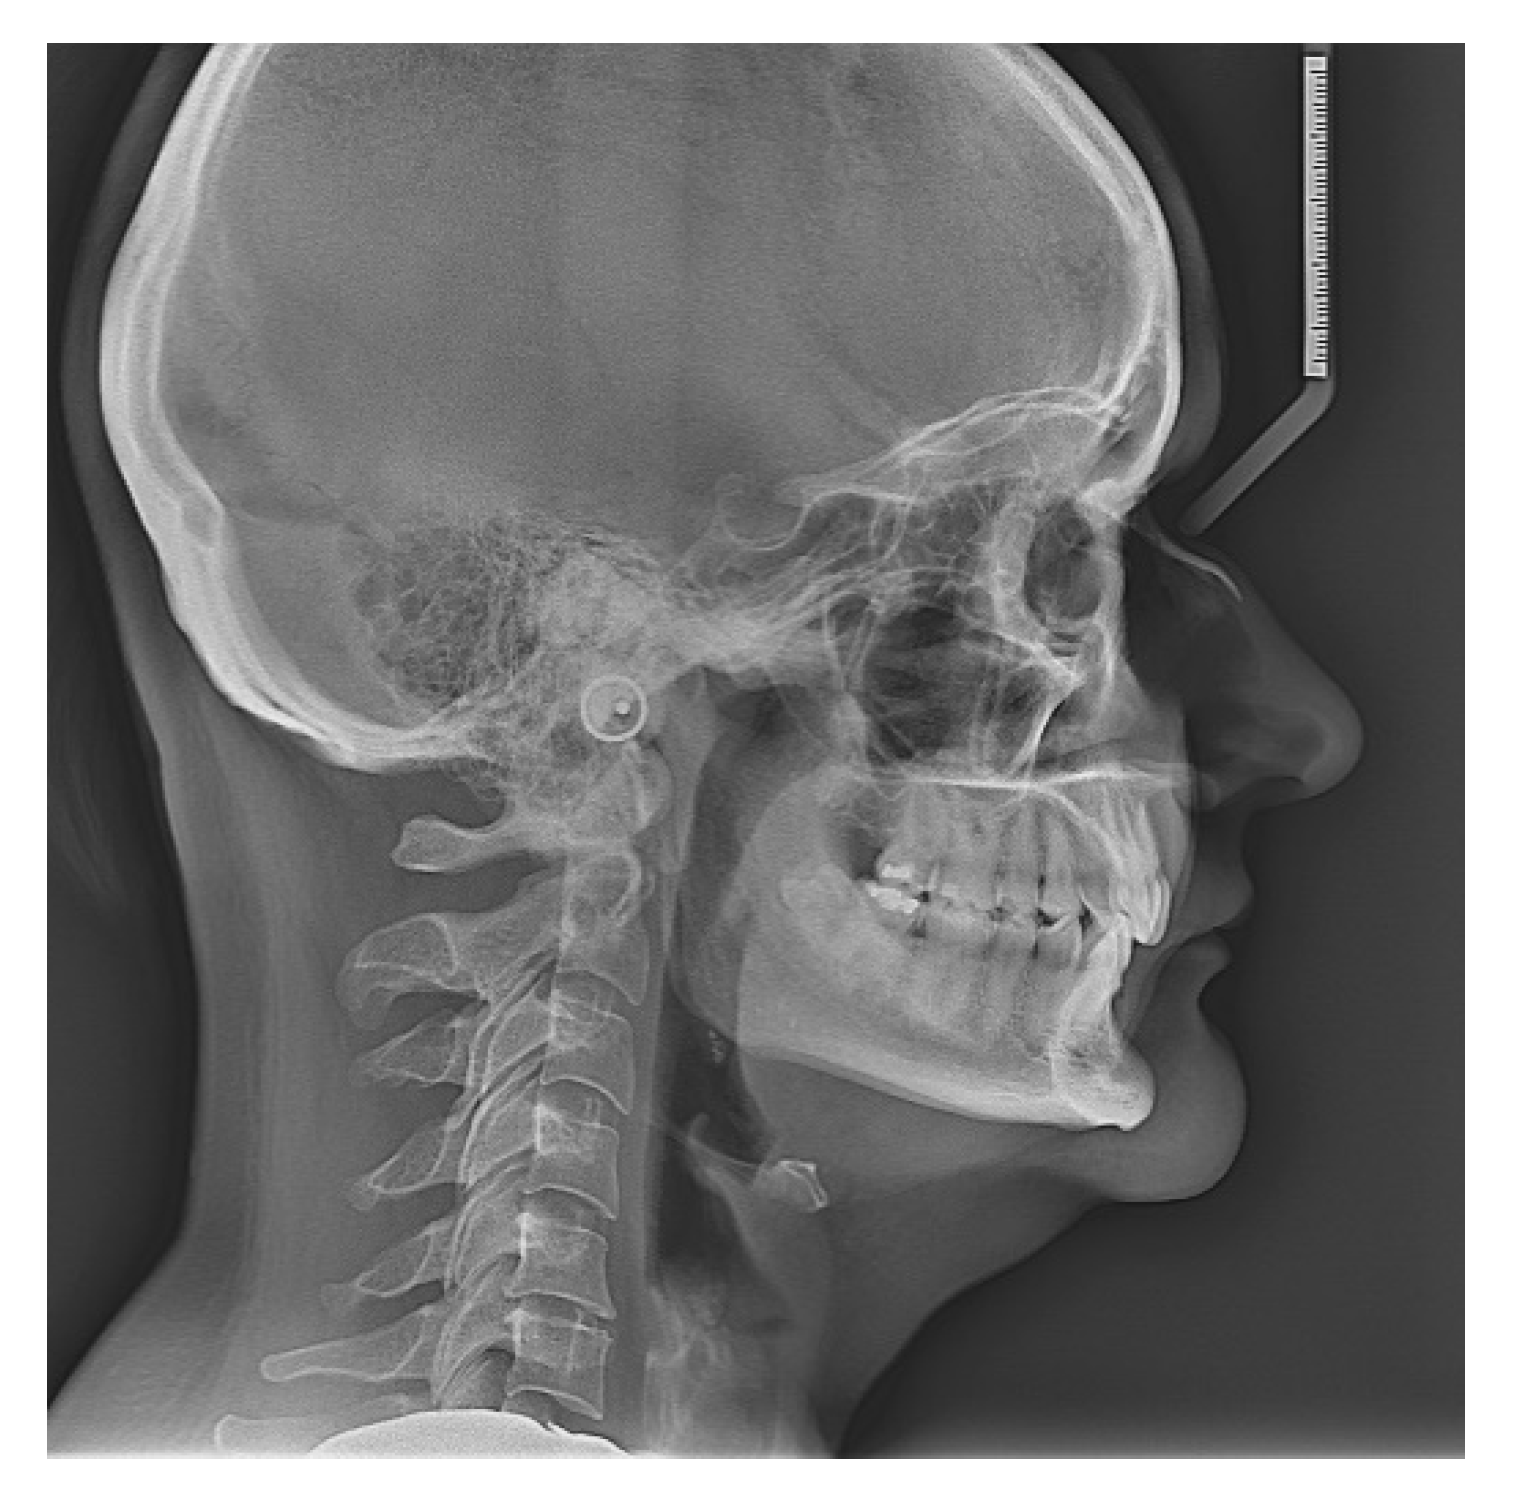

3.3. Case Report